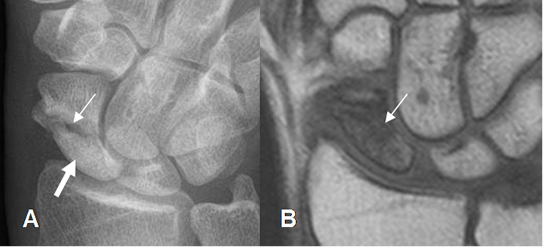

Fig 50. Fractura inestable del escafoides.

A: Rx AP y B: TAC axial de muñeca. Fractura oblicua e inestable en el polo inferior del escafoides, con fragmentos separados.